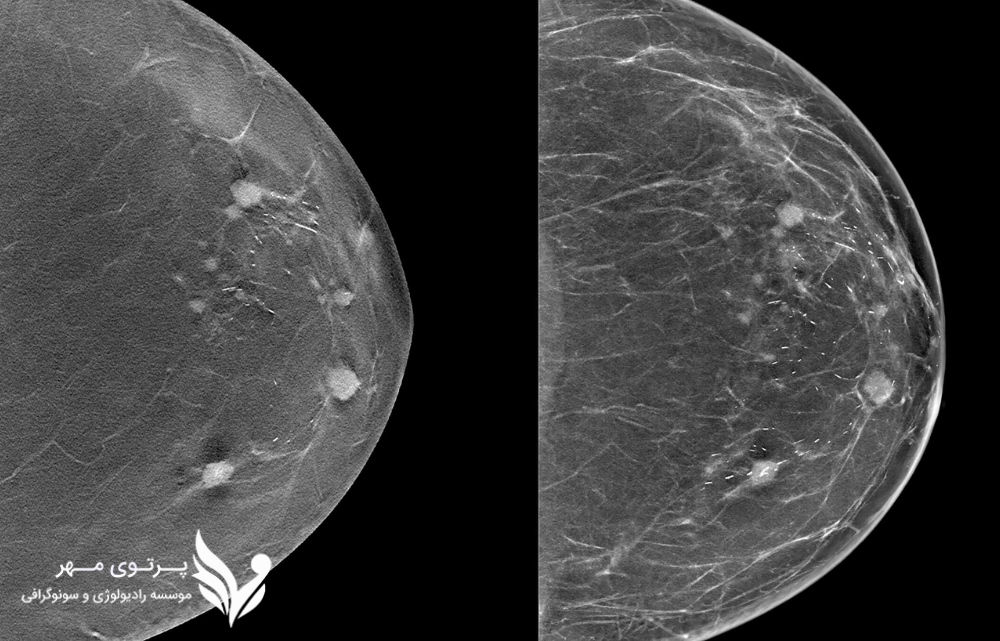

توموسنتز سه بعدی یا Digital Breast Tomosynthesis (DBT) یک روش نوین و پیشرفته برای تصویربرداری از سینه است که بهعنوان نسخهی تکاملیافتهی ماموگرافی شناخته میشود. برخلاف ماموگرافی دو بعدی سنتی که تنها یک تصویر از بافت سینه ارائه میدهد، در توموسنتز سهبعدی از سینه تصاویر متعددی در زوایای مختلف گرفته میشود. سپس این تصاویر با استفاده از الگوریتمهای رایانهای بازسازی شده و نمایی لایهلایه و دقیق از بافت سینه ایجاد میکنند.

تفاوت اصلی توموسنتز با ماموگرافی دو بعدی در این است که در روش دو بعدی، ممکن است تودهها یا ناهنجاریهای کوچک پشت بافتهای طبیعی سینه پنهان بمانند؛ اما توموسنتز سهبعدی این مشکل را با نمایش جداگانه هر لایه از بافت برطرف میکند. همین ویژگی باعث افزایش دقت تشخیص، کاهش نیاز به مراجعه مجدد و کاهش اضطراب بیماران میشود.

- کاهش اثر همپوشانی بافتها:در ماموگرافی دو بعدی، بافتهای سینه روی یک تصویر مسطح قرار میگیرند و ممکن است برخی ضایعات پشت بافتهای طبیعی پنهان شوند. توموسنتز با ایجاد تصاویر سهبعدی، این همپوشانی را کاهش داده و دید بهتری به پزشک میدهد.